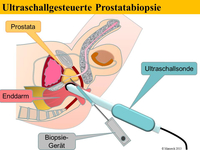

Im Allgemeinen spürt man den beginnenden Prostatakrebs nicht. Krankheitsspezifische Symptome werden erst in sehr späten Phasen der Erkrankung entwickelt. Um diese Symptome und die ernsthaften Folgen einer solchen Erkrankung zu verhindern, versucht man die Erkrankung frühzeitig zu diagnostizieren. Die wichtigsten diagnostischen Instrumente zum Nachweis eines Prostatakrebses sind die digital-rektale Untersuchung (DRU: Tastuntersuchung mit dem Zeigefingers des Arztes über den Enddarm), der PSA-Serumwert (ein Wert der durch eine einfache Blutabnahme ermittelt wird) und die transrektale Ultraschall-gesteuerte oder –gezielte Biopsie der Prostata.

Zunächst wird Ihnen der niedergelassene Urologe in der Region weiter helfen. Falls dieser den PSA-Wert für abklärungsbedürftig hält, wird er bei Ihnen ggf eine Probenentnahme der Prostata durchführen. Bringt eine solche erste, systematische Biopsie der Prostata keinen Tumornachweis und der PSA-Wert ist aber weiterhin auffällig bzw es gibt weiter Anlass für die Vermutung auf ein Prostatakarzinom, kann eine weiterführende Diagnostik mit innovativen, modernen bildgebenden Verfahren sinnvoll sein.

Die Methoden Ultraschall-Elastographie, der farbkodierte Doppler-Ultraschall sowie der kontrastmittelverstärkter Ultraschall und insbesondere die Echtzeit-MRT-Ultraschall-Fusion können helfen, auffällige Gebiete in der Prostata aufzuzeigen. So kann zum Beispiel ein in einer MRT (Magnetresonanztomographie) gefundener suspekter (also auffälliger) Bereich ganz gezielt biopsiert werden und auch zusätzlich noch elastographisch untersucht werden. Dies ist während einer herkömmlichen MRT-Untersuchung nicht möglich.

Eine multimodale Prostataabklärung erlaubt uns, die Prostata mittels modernster Verfahren zu untersuchen. Hierbei kommen verschiedene Untersuchungsmethoden zur Anwendung. Insbesondere die Echtzeitelastographie oder die kontrasmittelunterstützte Untersuchung der Prostata können hierbei wichtige Erkenntnisse über die Beschaffenheit der Prostata beisteuern. Auffällige Areale können in Echtzeit schmerzfrei mit lokaler Betäubung abgeklärt werden. Als Besonderheit können diese modernen Methoden auch mit einer bereits durchgeführten MRT-Untersuchung der Prostata fusioniert werden. Das bedeutet, in einer MRT gefundene auffälligen Areale der Prostata können zusätzlich mit modernsten Ultraschalluntersuchungen kombiniert untersucht werden und dann auch gezielt mittels gezielter Prostatabiopsie abgeklärt werden. Diese Untersuchung ist dann multimodal (zB Elastographie + konventionellem Ultraschall + MRT-Fusion).

Sie benötigen für die Probenennahme keine allgemeine Narkose. Bei der reinen Echtzeitelastographie benötigen sie keinerlei Art der Narkose. Da die Probenentnahme auch bei der MRT-Fusion und bei der Elastographie-gezielten Biopsie über den Enddarm (und nicht über den Damm) durchgeführt werden können, erlaubt eine haarfeine Nadel die vorherige Gabe von lokalen Narkosemittel eine ähnlich schmerzfreie Behandlung, wie sie ihnen der Zahnarzt bei einer Behandlung eines Zahnes gewährt. Das bedeutet: Sie selbst schlafen werden der Probenentnahme nicht, spüren jedoch keine Schmerzen.

Zunächst einmal werden die bereits durchgeführten und von Ihnen mitgebrachten MRT-Bilder (1,5T-3T, mit/ohne rektale Spule, DICOM-Format) in unser Gerät eingelesen. Anschließend werden die suspekten Areale und die Organgrenzen der Prostata in der MRT-Bildgebung markiert. Nun beginnt der praktische Teil: In angenehmer Seitenlage wird über einen modernen transrektalen Ultraschall die Prostata aufgesucht und anhand der Anatomie der Prostata mit dem MRT Bild fusioniert. Der Untersucher sieht nun auf der linken Seite des Flachbildschirmes des Ultraschallgerätes das Original-MRT-Bild mitsamt des Markierungen und auf der korrespondierenden rechten Seite die Live Ultraschallbilder in denen die Markierungen der MRT-Untersuchung zu sehen sind. Die auffälligen Areale können nun einer Elastographie oder einer Kontrastmittel-Untersuchung unterzogen werden um den Grad der Auffälligkeit zu bestimmen. Auf Wunsch können auch jetzt gleich die Biopsien durchgeführt werden.